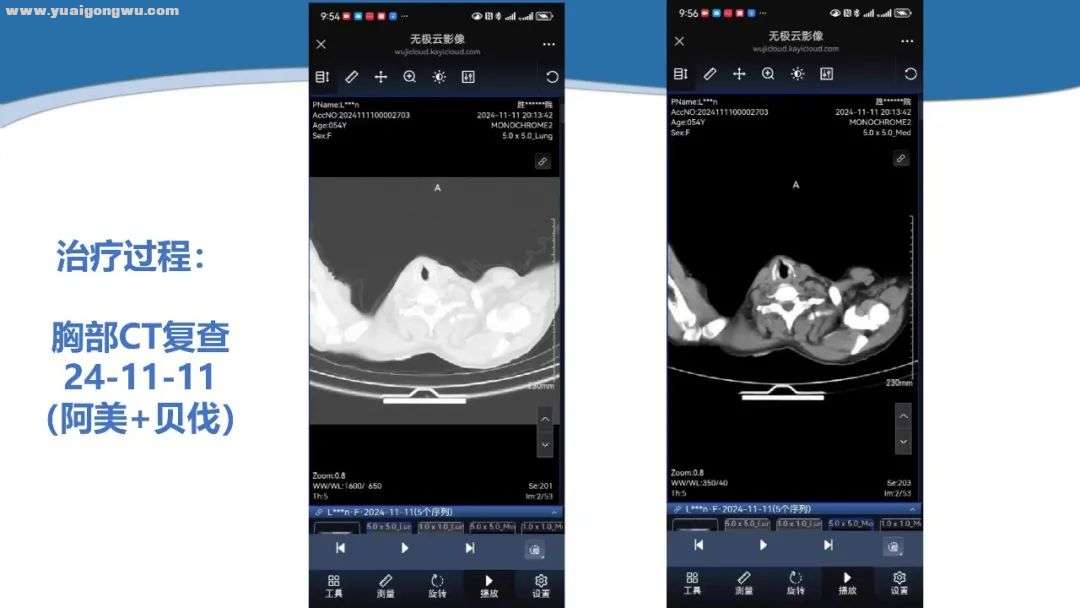

侯代伦教授 胸部CT两次检查结果变化不大,2024年11月至2025年3月胸腔积液量略有增加。虽肺内病灶是通过电脑传输影像查看,并非完全数字化影像,但更值得关注的是脑部磁共振变化。目前影像显示,患者左侧基底节区病灶较前增大,2025年3月15日与 2024年8月20日相比,病灶增大,增强扫描有血供且略增强,FLAIR成像呈高信号,范围也增大,由此判定颅内病变进展。